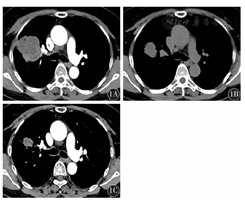

患者,女性,53岁,因右侧胸痛1个月余入我院。患者2017年6月无明显诱因出现右侧胸痛,无发热、咯血,无咳嗽、咳痰。既往体健,无吸烟史,无特殊基础病史。查体:体表面积1.51 m2,体能状态(PS)评分1分。神志清楚,精神尚可,浅表淋巴结未触及明显肿大。气管居中,颈静脉无怒张。双侧胸廓对称,双肺呼吸音清,无干湿性啰音及胸膜摩擦音。心率78次/min,律齐。实验室检查:血常规、癌胚抗原(CEA)、神经元特异性烯醇化酶(NSE)、细胞角蛋白21-1(CY21-1)、糖类抗原19-9(CA19-9)等均在正常范围;血生化:清蛋白39 g/L,谷氨酰转肽酶98 U/L,葡萄糖6.38 mmol/L,超敏C反应蛋白55.59 mg/L。胸部CT示:右肺上叶肿块,大小为6.4 cm×5.1 cm,考虑肺癌,右肺门及纵隔淋巴结轻度增大(图1)。头颅磁共振检查:右侧额叶及颞叶皮层下缺血灶,两侧上颌窦炎。外院上腹部CT检查示:左肾囊肿。进一步行肺穿刺活组织检查,病理免疫组织化学结果:AE1/AE(+++)、CK7(+/-)、p63(+)、p40(+)、CK5/6(少数+)、TTF-1(-)、NapsinA(-)、Ki-67(40%+)、SMA(-)、Desmin(-)、CD117(-)、CD34(血管+)、Vim(+)、S-100(+/-)。右肺为恶性肿瘤,分化程度差,倾向肉瘤样癌或多形性癌可能(图2)。临床分期cT3NxM0。肺组织基因检测示:表皮生长因子受体(EGFR)突变(第19号外显子);ALK、RET、ROS1、MET、HER2、KRAS、BRAF均未检测到突变;MYC基因扩增,TP53 C135Y突变,VEGFA基因扩增。经我院多学科综合诊疗(MDT)评估后,该患者于2017年7月19日开始接受化疗,方案为紫杉醇脂质体210 mg第1天+顺铂40 mg第1天至第3天,21 d为1个疗程,化疗2个周期。第1个周期化疗后肺部肿块缩小明显(图1B),2个周期化疗后肿块进一步缩小(图1),遂于2017年9月行VATS右上肺叶切除+淋巴结清扫术。术中切除右上肺叶,系统性清扫纵隔、肺门淋巴结。术后病理示:(右上肺)周围型结节型低分化癌(化疗后改变),大小为2.5 cm×2.5 cm×2.0 cm,显示低分化腺癌成分,癌成分占肿块的10%,坏死组织占肿块的90%,胸膜、支气管切缘、神经、脉管无侵犯,淋巴结0/14(图2)。术后病理分期:ypT1N0M0,ⅠA期。术后继续完成原方案2个周期辅助化疗,患者耐受差,终止进一步治疗,定期随访评估。截至2019年2月底,该患者未见复发转移,生命质量良好。